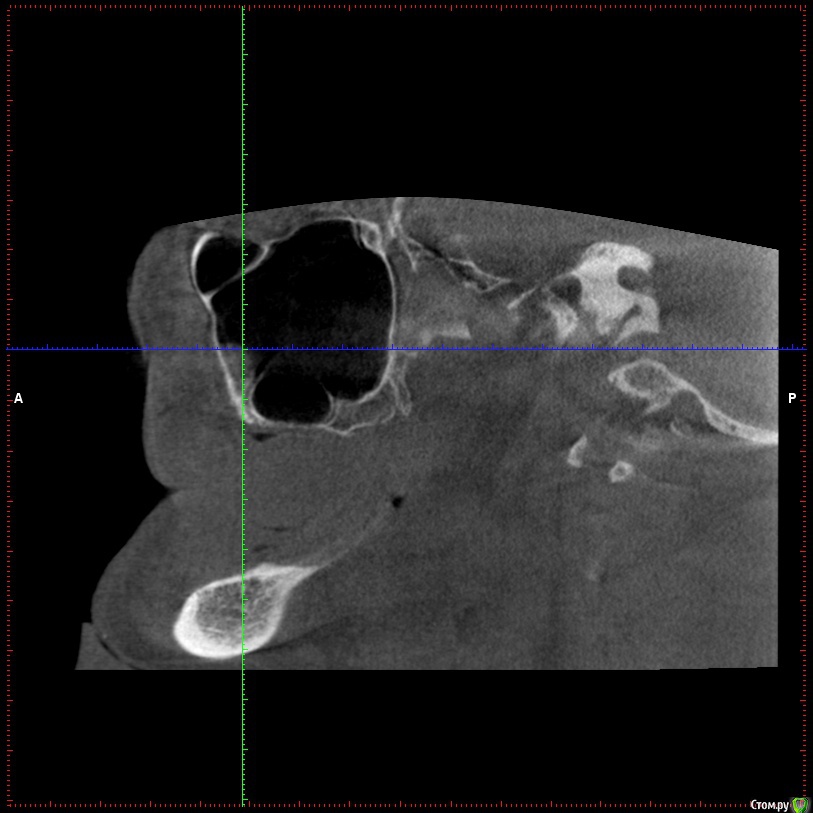

Aleksey_Mironov Опубликовано 11 января, 2018 Поделиться Опубликовано 11 января, 2018 здравствуйте коллеги!! вот такой сюрприз..хочу сделать синус лифтинг.. что за образование можеть быть? Ссылка на комментарий

Aleksey_Mironov Опубликовано 11 января, 2018 Автор Поделиться Опубликовано 11 января, 2018 здравствуйте коллеги!! вот такой сюрприз..хочу сделать синус лифтинг.. что за образование можеть быть? Ссылка на комментарий

Борис80 Опубликовано 11 января, 2018 Поделиться Опубликовано 11 января, 2018 Не совсем уверен, тк недостаточно срезов видно, но я бы сказал насморк или что-либо подобное(это по поводу тени) и , что значительно неприятнее, это костная перегородка на дне пазухи Ссылка на комментарий

колесников Опубликовано 11 января, 2018 Поделиться Опубликовано 11 января, 2018 (изменено) Может образоваться перфорация мембраны. Делайте 2 окна Изменено 11 января, 2018 пользователем колесников Ссылка на комментарий